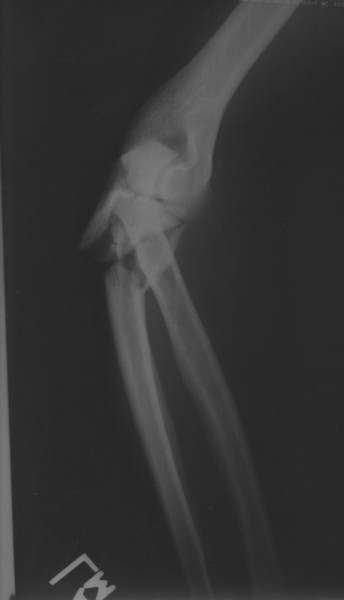

I fell eight feet onto a concrete floor. My left elbow was the first thing to hit, followed by my chest, chin, and knees. Yes. I remember that order very clearly. Chipped my right knee and broke my left arm just in front of the joint. At the hospital they operated to clean evreything up. Tuesday, the surgeon comes in to tell me what he plans to do.He said, " I've ordered some plates to go in your arm. You did a good job on it." I said, " So you are planning to tape this, and your procedure will become the standard for this repair? " He did not smile. He said very seriously, " Yes, that's how badly it's broken. Don't expect it to heal quickly." It didn't. It took four years and three more repair operations before the arm healed completely.

When I got home, I went to the emergency room to get the wound looked at. The ER physician looked at the X rays and said, " I' ve been working in this ER ten years, and I've never seen a bone broken this badly."